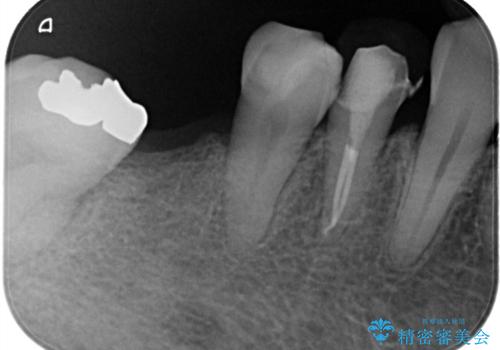

- 定期的に本院に通院されている患者様で、前歯の揺れがあると相談されました。下の奥歯が左右合わせて3本喪失されており、噛み合わせの負担が前歯にも集中していることを説明しました。右下6番の歯に関しては、事前の診査で十分な骨量がありましたのでインプラントを1本埋入しました。左下5番・6番にも本来はインプラントを埋入したかったのですが、骨量が十分でなく、骨を増やす処置をすると神経が近くリスクがあることから、審美性に配慮した金属のばねが見えないノンクラスプデンチャーを製作しました。また、このとき入れ歯を支える左下7番に根尖病変がありましたので、根管治療も行っております。(根管治療は当院院長で専門医を持つDr.林が担当しています。)治療終了後、約1年が経過しましたが、問題なく経過しており患者様も喜ばれていました。